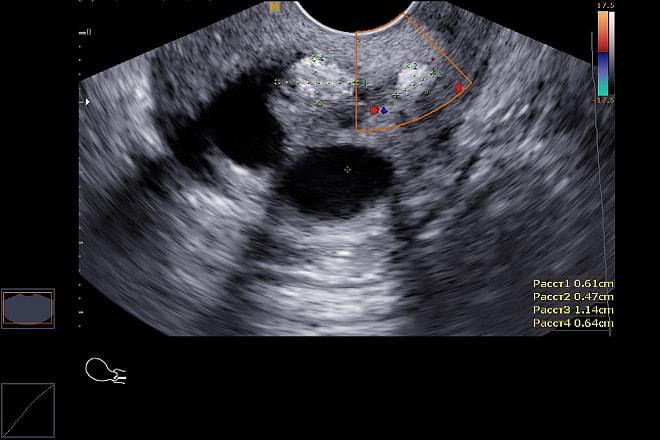

Гиперэхогенное образование представляет собой область с повышенной плотностью, которая хорошо видна при ультразвуковом исследовании. Для постановки точного диагноза врачу необходимо провести дополнительные обследования. Важно выполнить дифференциальную диагностику, чтобы исключить возможность злокачественных образований.

Эксперты в области гинекологии подчеркивают важность правильной диагностики гиперэхогенных образований в яичниках, так как они могут указывать на различные патологии. Гиперэхогенные образования могут быть как доброкачественными, так и злокачественными, поэтому их классификация и дальнейшее обследование имеют решающее значение. Врачам рекомендуется использовать ультразвуковую диагностику для определения характеристик образования, таких как размер, форма и структура. Дополнительные методы, такие как МРТ или КТ, могут быть необходимы для более детального анализа. Важно также учитывать клинические симптомы и анамнез пациентки, что поможет в постановке точного диагноза и выборе оптимальной тактики лечения. Эксперты акцентируют внимание на необходимости регулярных обследований, особенно для женщин в группе риска, чтобы своевременно выявить возможные осложнения.

Ультразвуковая диагностика: Ультразвуковое исследование (УЗИ) является основным методом диагностики гиперэхогенных образований. Специфические характеристики, такие как форма, размер и наличие дополнительных признаков (например, васкуляризация), помогают врачам отличить доброкачественные образования от злокачественных.

При проведении ультразвукового исследования (УЗИ) можно установить:

- размеры внутренних органов;

- состав крови;

- плотность и состояние тканей.